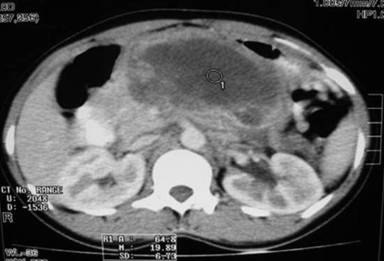

A 27-year-old married woman presented to our facility with abdominal pain and fullness of 20 days duration. She denied alcohol intake and she is a non smoker. There was no history of abdominal trauma or any drug intake for any other illnesses. Our clinical diagnosis was pancreatitis with fluid collection around the pancreas based on the serum amylase and lipase which were 720 U/L (reference range: 23-80 U/L) and 210 U/L (reference range: 0-60 U/L), respectively. CT scan of abdomen revealed huge hypodense lesion in pancreas suggestive of pseudocyst. (Figure 1). Patient also had a small 3x3 cm swelling over the right jaw. We subjected the patient for endoscopic ultrasonography (EUS) which revealed a 6x6 cm cystic lesion involving head and body of pancreas. There was no gallstones visualized. As the EUS showed irregular borders of the cyst we did cyst fluid aspiration for analysis (Figure 2). Cyst fluid amylase, CA 19-9, and CEA were 13,500 U/L, 28 U/mL, and 17 ng/mL, respectively. Cytological examination (fine needle aspiration; FNA) showed large, pleomorphic mononucleated cells having large, hyperchromatic, pleomorphic nuclei and moderate to ample amount of pale or vacuolated cytoplasm and a multinucleated giant cell at the center suggestive of choriocarcinoma (Figure 3). Biopsy of the lesion in left jaw also revealed germ cell tumor. Serum beta human chorionic gonadotropin was 98,000 mg/dL. Interestingly, alpha-fetoprotein was 9.6 ng/mL which excluded other giant cell tumors except choriocarcinoma. Choriocarcinoma is a germ cell tumor which presents with normal alpha-fetoprotein and very high beta human chorionic gonadotropin levels.

Figure 1. Contrast enhanced computerized tomogram of abdomen showing huge hypodense lesion in pancreas suggestive of pseudocyst (circle#1). |